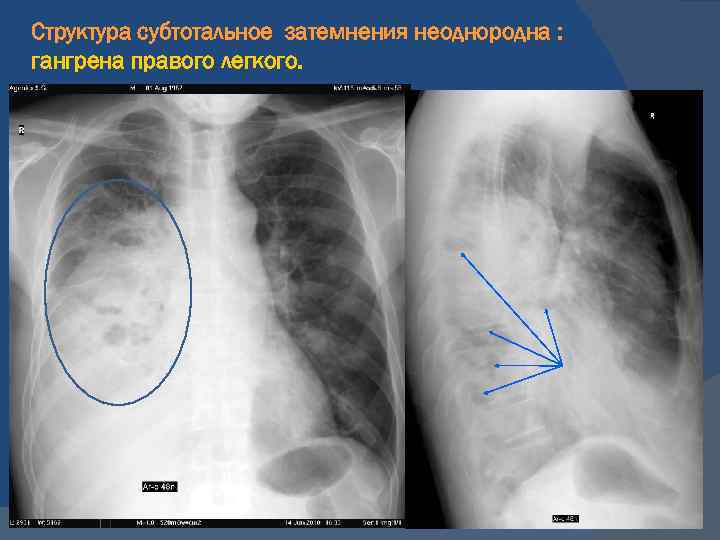

Рентгенологические изображения и синдромы патологии легких